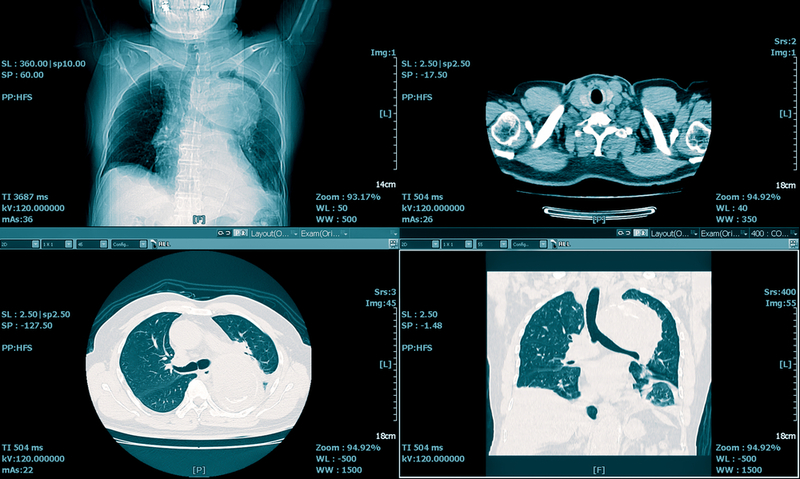

For each of the 21 patients, the initial CT scan was evaluated for the following characteristics: (1) presence of ground-glass opacities, (2) presence of consolidation, (3) number of lobes affected by ground-glass or consolidative opacities, (4) degree of lobe involvement in addition to overall lung "total severity score," (5) presence of nodules, (6) presence of a pleural effusion, (7) presence of thoracic lymphadenopathy (lymph nodes of abnormal size or morphology), and (8) presence of underlying lung disease such as emphysema or fibrosis. Any other thoracic abnormalities were also noted.

The analysis showed that 2019-nCoV typically manifests on CT with bilateral ground-glass and consolidative pulmonary opacities. Nodular opacities, crazy-paving pattern, and a peripheral distribution of disease may be additional features helpful in early diagnosis. The researchers also noted that lung cavitation, discrete pulmonary nodules, pleural effusions and lymphadenopathy are characteristically absent in cases of 2019-nCoV.

Follow-up imaging in seven of eight patients showed mild or moderate progression of disease as manifested by increasing extent and density of airspace opacities.